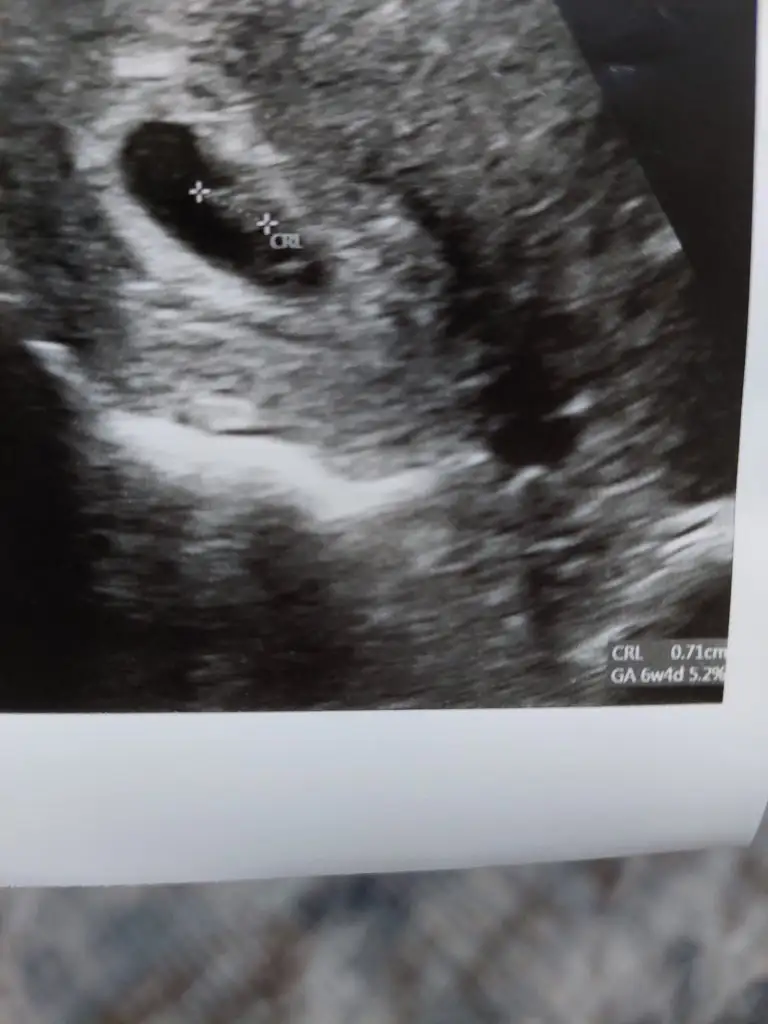

kuzum buna tahminde bulunamadım, 6 haftalıkkrb yolk kesen görünüyor zaten diğerinde de bebek üstü yazılarla kapalıCanım benim de 6 haftalıkken bu ultrasonum yorum yapabilir misin diğeri 8 haftalıktı

bebek göremedim yolk saç var canım maalesef yorum yapamam5+5 burada banada bakar mısın